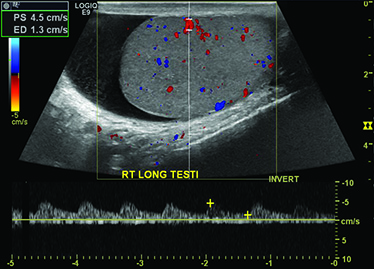

A 61-year-old male comes to the emergency department complaining of gradual onset of worsening right scrotal swelling. He first noticed the swelling about 1.5 weeks ago. There have been no fevers, chills, discharge, or dysuria. The pain is not exacerbated with coughing or sexual activity. His vital signs are normal. His right testicle is markedly enlarged when compared to the left. The testicle is tender to manipulation, but has no erythema or calor. Neither a Prehn sign nor a cremasteric reflex are present. There are no scrotal or penile skin lesions, no hernia, and a urinalysis is normal. A formal scrotal ultrasound is obtained, which reveals a large cystic lesion within the right scrotum, a moderately sized right hydrocele, and a small epididymal head cyst. There is no evidence of torsion (Image 1). The patient is safely discharged with instructions to follow up with an urologist as an outpatient in 3-5 days.

Image 1. Color Doppler sonogram of our patient's right testicle displaying normal arterial vascular flow and presence of a hydrocele. The ultrasound report also mentioned the presence of an epididymal cyst and a cyst within the testicle (not shown).